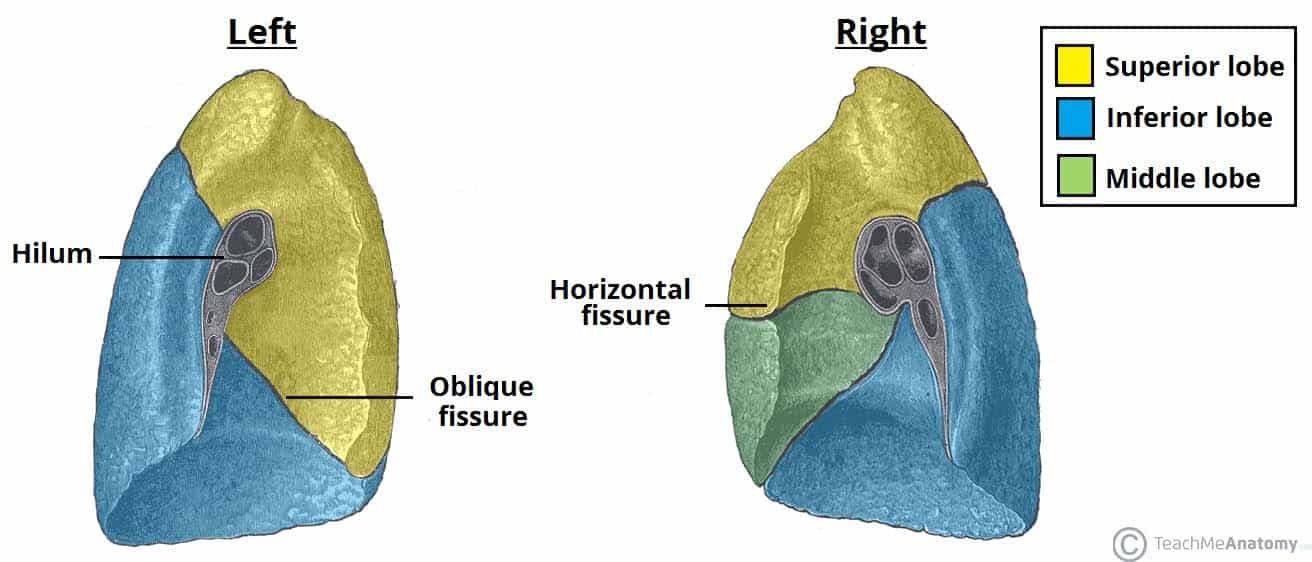

lung lungs lobes fissures middle inferior divided thorax

lungs lobes fissures right left oblique both teachmeanatomy lung structure thorax fig similar position info

Lungs lobes fissures right left oblique both teachmeanatomy lung structure thorax fig similar position info. Pin on bronchial anatomy. Topography of the lungs (posterior view) the apex of the lung extends